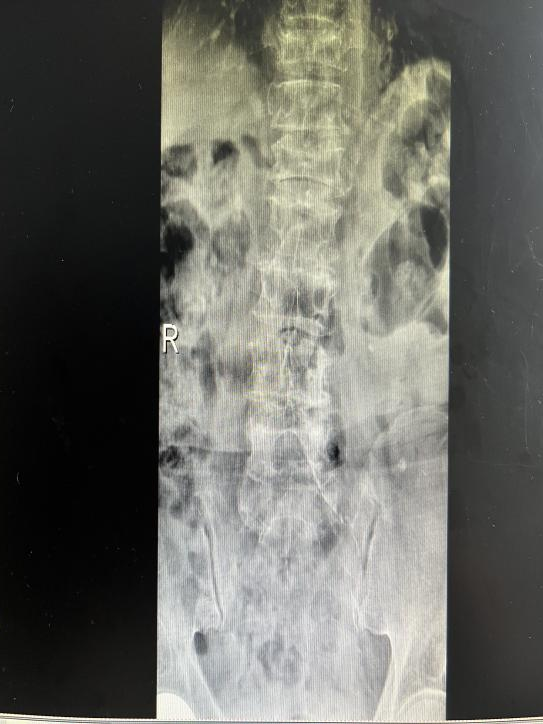

12月17日,贵州航天医院第88次晨读会由我院骨一科主任、副主任医师陈明勇作学术交流,他以“肱骨近端骨折并肩关节脱位的手术治疗”为题,全面讲解了该损伤的手术策略、术中血供保护理念及内侧支撑重建技术等内容,并通过多个典型病例图文资料分享了从损伤机制分析、手术步骤实施到术后随访评估的完整过程与关键细节,为临床处理此类复杂骨折提供了较为全面的技术参考,有助于在手术规划中结合个体情况开展针对性治疗。 贵州航天医院 骨科专家简介 陈明勇 骨一科主任,副主任医师 临床擅长:从事创伤骨科工作约20年,对骨缺损、骨不连、骨肿瘤、肢体畸形等的肢体矫形重建及功能重建,慢性化脓性骨髓炎的根治治疗、糖尿病足的保肢治疗、快速康复理念(ERAS)下的老年骨折的诊治,四肢复杂骨折的诊治,四肢骨折等微创手术治疗具有丰富的临床经验。 2004年毕业于遵义医学院临床专业,曾在中国人民解放军总医院、广西医科大学第一附属医院、上海第六人民医院骨科进修。中国中西医结合学会骨伤科专业委员会横向骨搬移治疗糖尿病足及微血管网再生学组首届委员,遵义市医学会创伤分会常务委员。 瞿 晖 骨科党支部书记,骨二科主任,副主任医师 临床擅长:对骨科的常见病、关节外科、脊柱外科及运动医学疾病的诊治具有丰富的临床经验,熟练掌握骨科手术操作技术。 毕业于遵义医学院临床医学系,2005年前往广州中山大学第一附院骨显微医学部进修学习,2011年前往成都华西医院进修学习,并多次在省内外学习骨科相关知识,是中华医学会骨科分会会员。 赵小锋 中共党员,骨二科副主任,副主任医师 临床擅长:从事骨科临床工作11年,对骨科常见病、多发病诊疗有较为丰富的临床经验,擅长脊柱相关疾病诊断及治疗,尤其是颈、腰、腿疼痛疾病诊断及治疗,擅长胸腰椎骨折微创经皮穿刺内固定术、经皮穿刺椎体成形术、经皮穿刺脊柱内镜下腰椎间盘摘除术、单纯开创腰椎间盘摘除术、腰椎滑脱复位椎间植骨椎融合内固定术、腰椎管狭窄减压融合内固定术及人工髋、膝关节置换术等。 2012年毕业于遵义医学院外科学专业硕士研究生,2019年参加“遵义市115医学人才精英计划”于上海交通大学第一附属医院培训学习,2023年于北京大学第三人民医院脊柱外科进修学习,曾获得遵义市优秀医师荣誉称号。 遵义市手外科第一届委员,遵义市医学会创伤分会第一届委员,遵义市医学会创伤分会第二届委员,贵州省康复医学会第三届脊柱脊髓专业会委员,遵义市医学会烧伤与整形外科学分会委员,发表论文5篇,其中国家级核心期刊1篇,SCI论文1篇,主持市级课题1项并结题,参与市级课题2项。 赵兴东 骨科主任医师 临床擅长:擅长骨科的常见病及各种创伤、四肢骨折创伤修复、骨感染、手足疾病的诊治和手足体表畸形的矫形整复,熟练掌握骨科四肢骨病及创伤的手术操作技术,尤其在四肢关节复杂性损伤、手足外伤、组织缺损创面、难治创面的皮瓣修复方面及平足、高弓足矫形方面及四肢慢性疼痛诊治、康复方面具有丰富的临床经验。 硕士研究生,毕业于遵义医学院临床外科系,2015年前往山东省立医院手足外科进修学习;遵义市医学分会创伤分会第一、二届委员,遵义市手外科医学会第二委届员会常务委员;在省级及省级以上期刊发表文章9篇,参编著作2部,参与主持并完成市级课题1项,参与市级课题2项、省级课题1项。 张艳金 中共党员,骨科副主任医师 临床擅长:从事骨外科工作16年,对复合伤、多发伤的救治、四肢骨干骨折、关节周围骨折、骨肿瘤、骨髓炎等诊治具有丰富的临床经验。 中共党员,硕士研究生,2006年本科毕业于山西医科大学第二临床医学院,2011年研究生毕业于北京军区总医院;在“老年COPD患者合并髋部骨折的诊治”国际合作课题组研究两年,在老年髋部骨折的诊治方面具有丰富的经验,并发表论文6篇;主持遵义市级课题1项,承担遵义医科大学的临床教学工作,获得遵义医科大学优秀带教老师荣誉。编撰有《骨科疾病诊疗精粹》一书,开展2项新技术,编撰地方规范《务川自治县创伤骨科常见疾病诊疗规范》一书。 张俊凯 骨科副主任医师 临床擅长:从事骨科临床工作28年,对创伤骨折、骨感染、骨缺损、骨不连等外科诊治,四肢骨折的微创手术治疗,四肢复杂骨折(如关节内粉碎性骨折、多发骨折等)的损伤控制及手术治疗等具有丰富的临床经验。 1995年毕业于遵义医学院临床专业,2009年前往复旦大学附属医院骨科进修1年。 卢懿明 中共党员,骨科副主任医师 临床擅长:从事骨科工作18年,对创伤骨折、四肢骨折的微创手术治疗、四肢复杂骨折(如关节内粉碎性骨折、多发骨折等)的损伤控制及手术治疗,尤其是髋部骨折的PFNA等微创技术,踝关节骨折、膝关节周围骨折的Mipo微创技术等具有丰富的临床经验,开展了4项新技术,发明6项新型专利技术。 2005年毕业于遵义医学院临床专业,2017年,前往南方医科大学第三附属医院骨科进修半年,回院后运用Mipo技术对骨干骨折及干骺端骨折的治疗技术,同时积极开展骨盆骨折、髋臼骨折腹直肌外侧切口的应用;发表了多篇专业论文,经常参与省内外学术交流会授课,获得医院荣誉称号多个。 邬夏荣 骨科副主任医师 临床擅长:从事骨科工作16年,对四肢复杂骨折、骨肿瘤的诊治,尤其是足踝创伤、慢性踝关节损伤、平足症等诊疗具有丰富的临床经验。 2006年毕业于遵义医科大学临床医学专业,曾在陆军军医大学西南医院进修学习,发表多篇骨科学术论文。 余德怀 中共党员,骨科副主任医师 临床擅长:从事骨科工作10余年,对运动医学、骨关节、脊柱外科常见病、多发病的诊治具有丰富的临床经验。 硕士研究生,2011年毕业于遵义医学院临床医学专业,曾前往遵义医科大学附属医院运动医学专业进修学习;是贵州省医学会运动医学分会青年委员,西部关节镜联盟委员;发表多篇骨科学术论文。 冯 乾 骨科副主任医师 临床擅长:从事骨科工作近20年,熟练掌握骨科多发病及常见病的诊治,尤其对脊柱退变性疾病的诊断及治疗具有丰富的临床经验,主要研究脊柱微创相关治疗方式,能熟练开展椎间孔镜及UBE。 曾前往北京大学第三医院进修学习疼痛及椎间孔镜、首都医科大学友谊医院专业进修脊柱内镜;是贵州省康复医学会第三届脊柱脊髓专业委员会委员;发明专利3项、发表脊柱外科专业论文多篇。 贵州航天医院骨科简介 基本情况 贵州航天医院(原3417医院)骨科组建于1968年,前身是以创伤和断肢(断指)再植闻名于世的上海市第六人民医院骨科,中国断肢(断指)再植的奠基者、中科院院士陈仲伟等专家莅临科室指导医疗和教学,并在70年代开展了贵州省首例断肢(断指)再植手术。组建50余年来,诊治患者已逾百万,挽救了无数的伤病员,成为了保障遵义地区人民群众健康的重要支撑。 经过几代人的不懈努力,今天的骨科,已由创伤骨科发展至骨病、骨肿瘤、骨结核等领域,现有脊柱外科、关节外科、四肢创伤、手足外科四个亚专科,成为了集医疗、教学、科研于一体的综合学科,是贵州省临床重点专科、遵义市临床重点专科、遵义市骨科临床医学中心、遵义市基层骨科专科联盟理事长单位。 科室目前开放床位110张,共有医护人员50余人,副高级以上专家18人,硕士研究生15人。拥有一流骨科医疗设备多台,每年不定期选派优秀技术骨干到全国各大知名医学院校进修、学习、参观、交流,并邀请国内、国外知名专家教授来院进行交流、指导,通过不断引进国内外先进的诊疗技术,科室医疗技术水平稳步提升,为广大人民群众提供了优质的医疗服务。 专科特色 骨一科 (一)骨缺损、骨不连的肢体与功能重建 胫骨横向骨搬移技术治疗糖尿病足: (二)慢性骨髓炎的根治治疗 (三)肢体缺血性疾病如糖尿病足、脉管炎的保肢治疗 (四)皮瓣修复 (五)复杂创伤的治疗 (六)老年髋部骨折及小儿骨折快速手术 老年髋部骨折: 骨二科 (一)胸腰椎骨折微创经皮椎弓根螺钉固定术 (二)老年性骨质疏松性患者腰椎滑脱脊柱内固定术(骨水泥螺钉) (三)V形双通道脊柱内镜技术(VBE)腰椎融合术治疗腰椎退行性疾病 (四)老年性骨质疏松性骨折(PVP/PKP)术 (五)人工髋关节置换术 (六)双侧股骨头坏死人工全髋关节置换 (七)右侧全髋置换术后假体周围骨折翻修 (八)人工膝关节置换术 (九)人工膝关节假体松动翻修 (十)关节镜技术 传统手术切口 关节镜技术切口 诊疗范围 骨一科 1.四肢创伤、矫形。 2.手、足踝外科。 骨二科 end